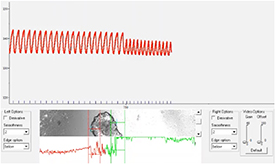

CSs bioprinted in 4% Al/8% Ge hydrogel contracted spontaneously and upon electrical stimulation. The spheroids demonstrated spontaneous beating frequencies in the physiological range of 0.3 and 1.2 Hz, corresponding to beating rates between 18 and 72 beats per minute (figure 6 and video 6). Contraction of CSs bioprinted in the CardioExcyte plate induced gel movement as can be observed in video 7. Bioprinted CSs also exhibited propagation of the electrical impulses, demonstrating interspheroid functional coupling as seen in video 8. Figure 7 shows the EFP and impedance signals recorded from spontaneously beating CSs bio-printed in the CardioExcyte plate. The EFP reflects their electrical activity and the impedance amplitude represents an indirect measure of contractility [22, 33]. The recording demonstrates that the spheroid constructs exhibited robust synchronous electrical activity and contractile behavior sensitive to the compound treatment. Addition of isoproterenol (1 μM) shown in figure 7 resulted in the increased spontaneous beating rate induced by adrenergic stimulation.

Figure 6. Field potential stimulation of a bioprinted CS. Field potential stimulation between 0.6 and 1.2 Hz was applied to record the contraction–relaxation function in bioprinted CSs using motion tracking (see also video 6).

Standard image High-resolution imageFigure 7. Electrical recording from bioprinted CSs using the CardioExcyte96 plate. Phase contrast image of bioprinted CSs in proximity of the electrode at the center of a well in a CardioExcyte96 plate (left). Representative measurements of raw mean beat impedance and field potential waveforms shown before and after addition of 1 μM isoproterenol to bioprinted CSs. Please refer to videos 7 and 8 for live recording.

As the use of in vitro bioprinted spheroids for pharmacological testing requires detectable contractile function, we evaluated how to detect it with two different methods developed by us. In our first approach, we used a Ionoptix system to measure spontaneous contractile activity and under field potential (figure 6 and video 6). While we were not able to measure any contractile activity in 3D bioprinted single cells, our physiological testing using cardiac cells determined that 4% Al/8% Ge hydrogels were permissive for intrinsic contractile function (figure 6 and video 6). Bioprinted spheroids displayed spontaneous contraction towards their center. However, these movements were very small and difficult to detect. The edges of the spheroid were largely unaffected by the intrinsic contraction and it was not possible to measure any contraction. However, these CSs responded by synchronous contraction to electrical stimulation. This may be due to the close proximity of the cells in the spheroid allowing for intracellular communication and formation of electroconductive networks [18]. The presence of connexin 43 in bioprinted CS, together with cardiac troponin T (figure S6), both cardiac specific markers and essential for optimal cardiac tissue conductivity and contractility was supporting the ability of the CS to contract as a whole tissue. Spheroids could be paced between 18 and 72 beats per minute (0.3–1.2 Hz) spanning bradycardic and normal heart rate ranges in humans. This suggests that 3D bioprinted CSs have the potential to investigate long- and short-term effects of pharmaceuticals on the human heart, a much needed response to provide novel pathophysiological tools for cardiovascular drug discovery and toxicity [5, 34].

The EFP signal recording from spheroids showed that their electrical activity was sensitive to isoproterenol (figure 7). However, the concomitant decrease in contractile signal indicated that bioprinted CSs still retain a negative force–frequency relationship known for iPSC-derived cardiomyocytes. Electrical stimulation of iPSC-CMs has been shown to improve their maturation status and function [11]. A similar approach could be applied to the CSs bioprinted in the new CardioExcyte plate with built-in electrical stimulation to improve their performance and utility for drug testing.